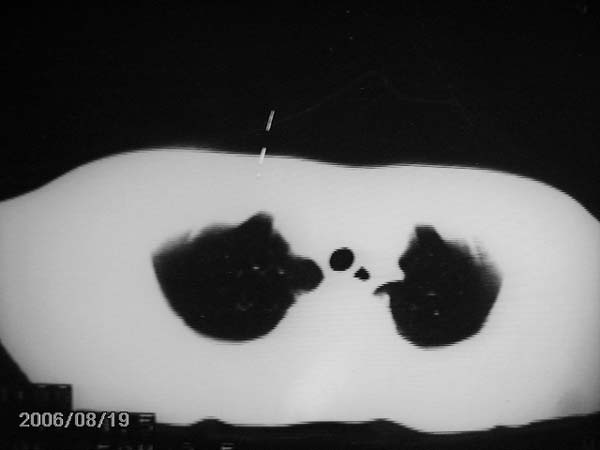

男,13岁,发烧半月,干咳无痰,正规使用抗生素半月,现在仍是午后低烧!!!未做痰检

结合临床考虑:右肺中叶结核可能性大.

右肺中叶结核可能性大

右肺结核,右肺中叶不张

右侧肺门淋巴结好象有增大,会不会是个原发综合症合并感染

右中肺呈大片状密度欠均匀影,内见含气支气管.

结合病史,考虑:右中肺大叶性肺炎(吸收期).

右肺中叶大片状密度增高影,内密度不均匀,右肺门处增大,应该是淋巴结肿大,结合临床首先考虑原发性肺结合可能性大,不排除合并感染可能,建议治疗后复查.